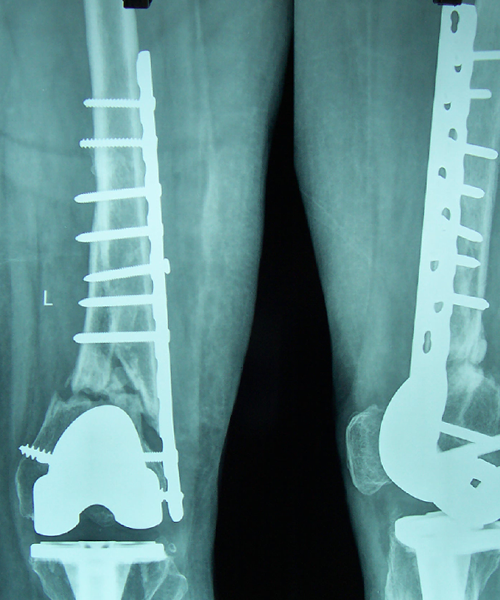

Case:14 Periprosthetic Fracture

60 years old patient with total knee replacement on left knee presented with open grade 1 injury. Debridement & slab given on emergency bases. Fixation with plate & screws done. Union was seen after 6 months.

Pre-Op AP

Pre-Op Lat.

Immdiate Post-op

1 and half months Post-op

2 and half months Post-op

3 and half months Post-op

4 and half months Lateral

6 Years Follow-Up